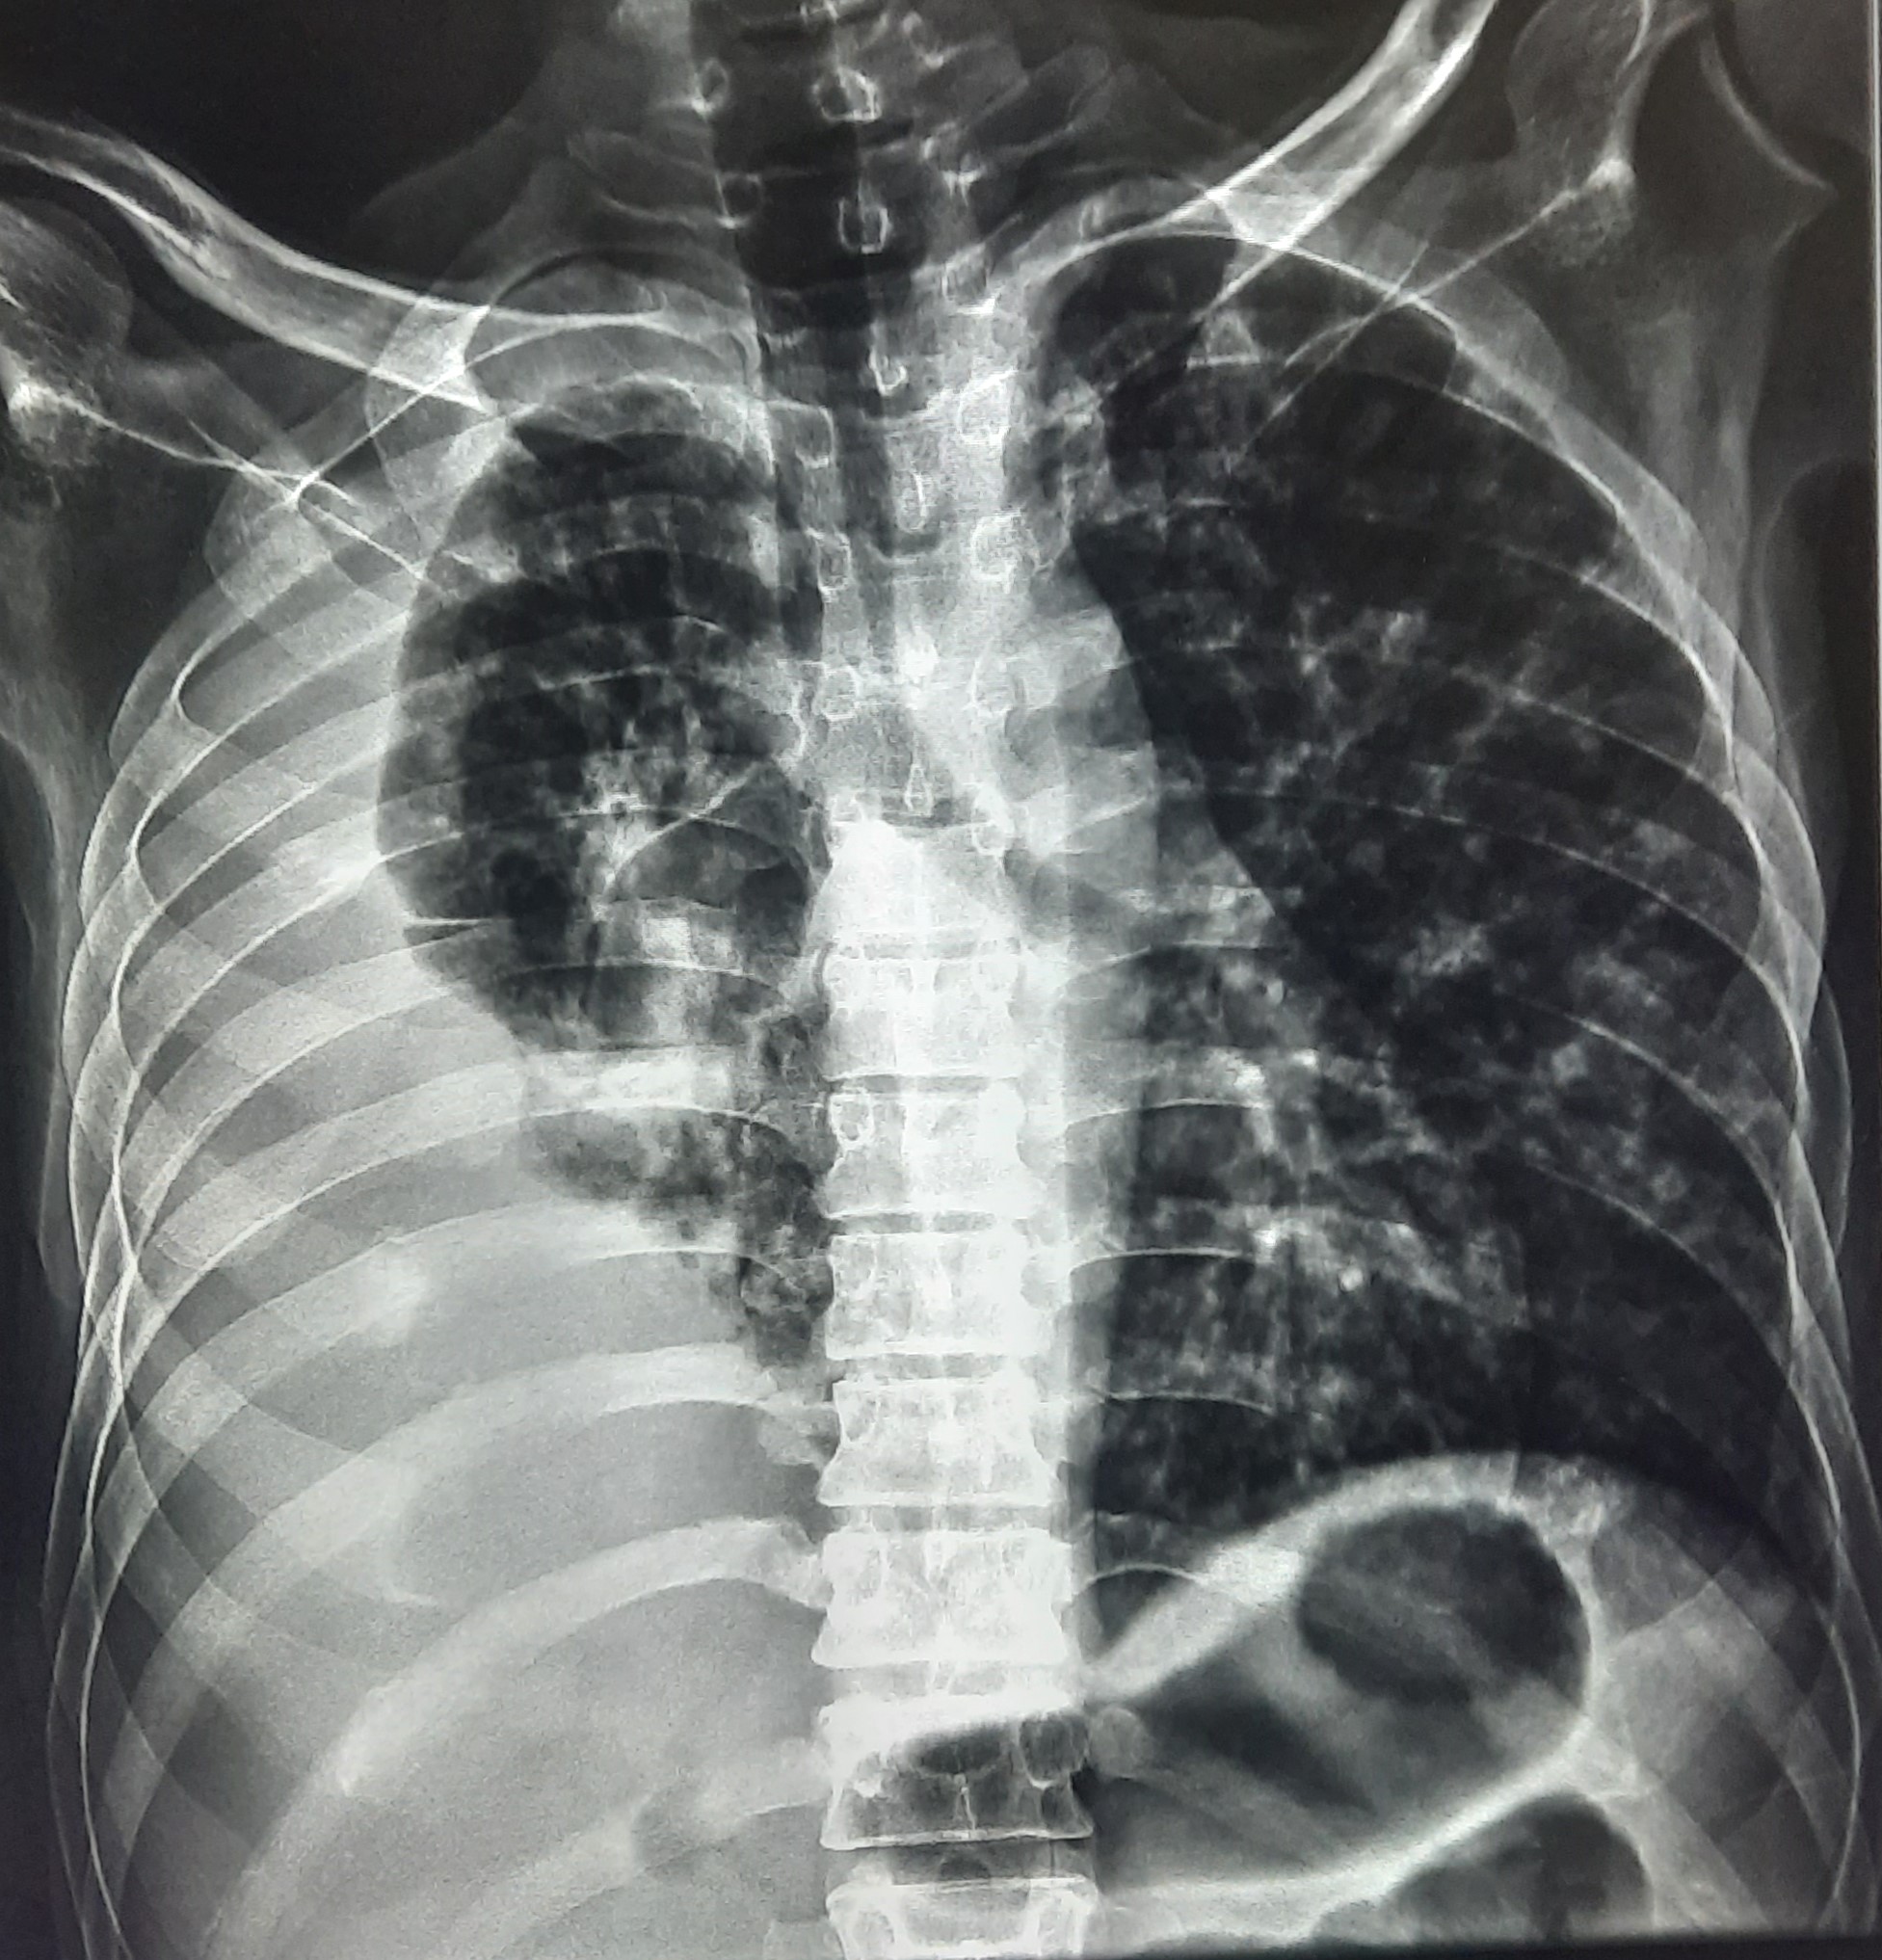

| 52 | IGGMC, Nagpur, Nagpur | P2 | 29-4420 | Hamida Bano | Consent taken on Paper | 56 Yrs. |

Provisional Diag : Post TB Sequelae With Reactivation?

Final Diag : Post TB Sequelae |

Post TB Sequelae | Tracheal Pull Left Side, Left Mid Zone & Upper Zone Fibro cavitary Lesion Present, Compensatory Right lung Hyper Infiltration Present, Few ill-defined Bilateral Lung Opacity Presnt | Abnormality visible on x-ray |